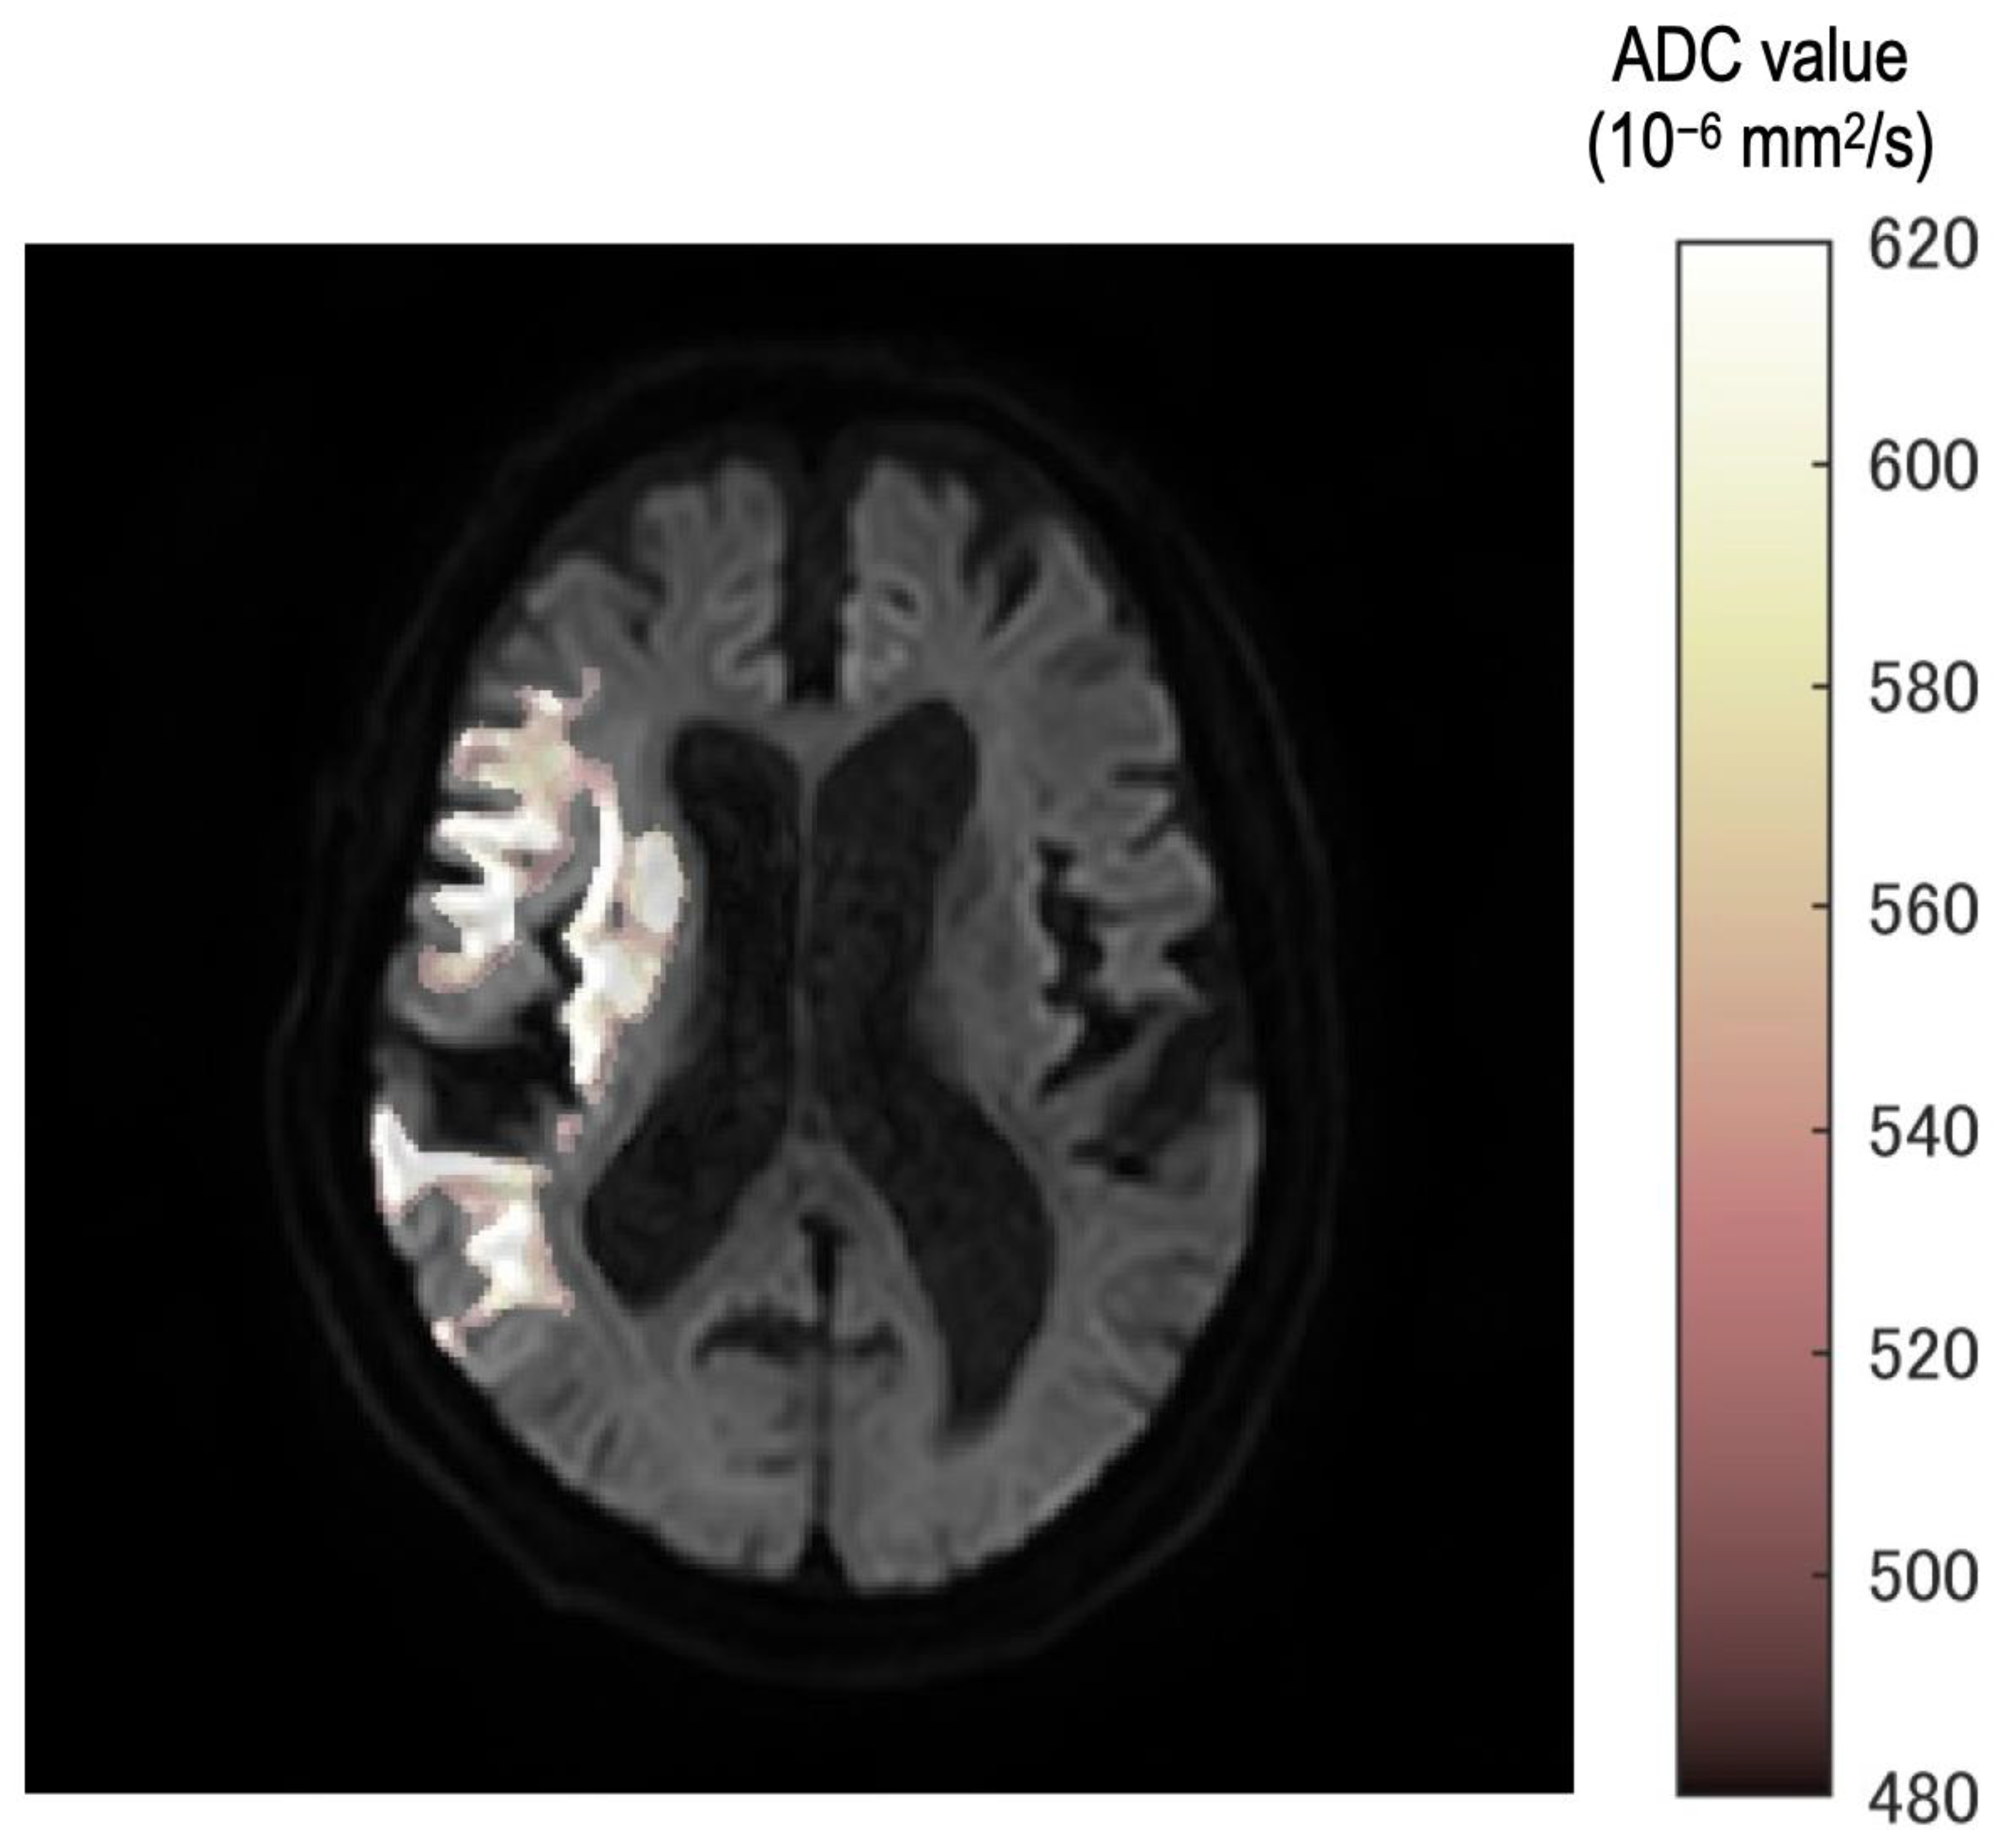

In all cases, the neurosurgeon confirmed the consistency between the occlusion point and ROI using the fusion image (Figure 2). Furthermore, fusion images between DWI with b = 1000 s/mm2 and each ROI of the ADC value were created automatically.

Figure 2.

The fusion image ROI of each threshold and b = 1000 image. Stepwise color tone changes can be observed according to the ADC value. All images were reviewed by the neurosurgeon for any differences from the occlusion point.

In the fusion image, the discrepancy of threshold was described as a gradual color change from white to deep red. Therefore, observers can understand the discrepancy as texture according to the threshold in the ischemic region.